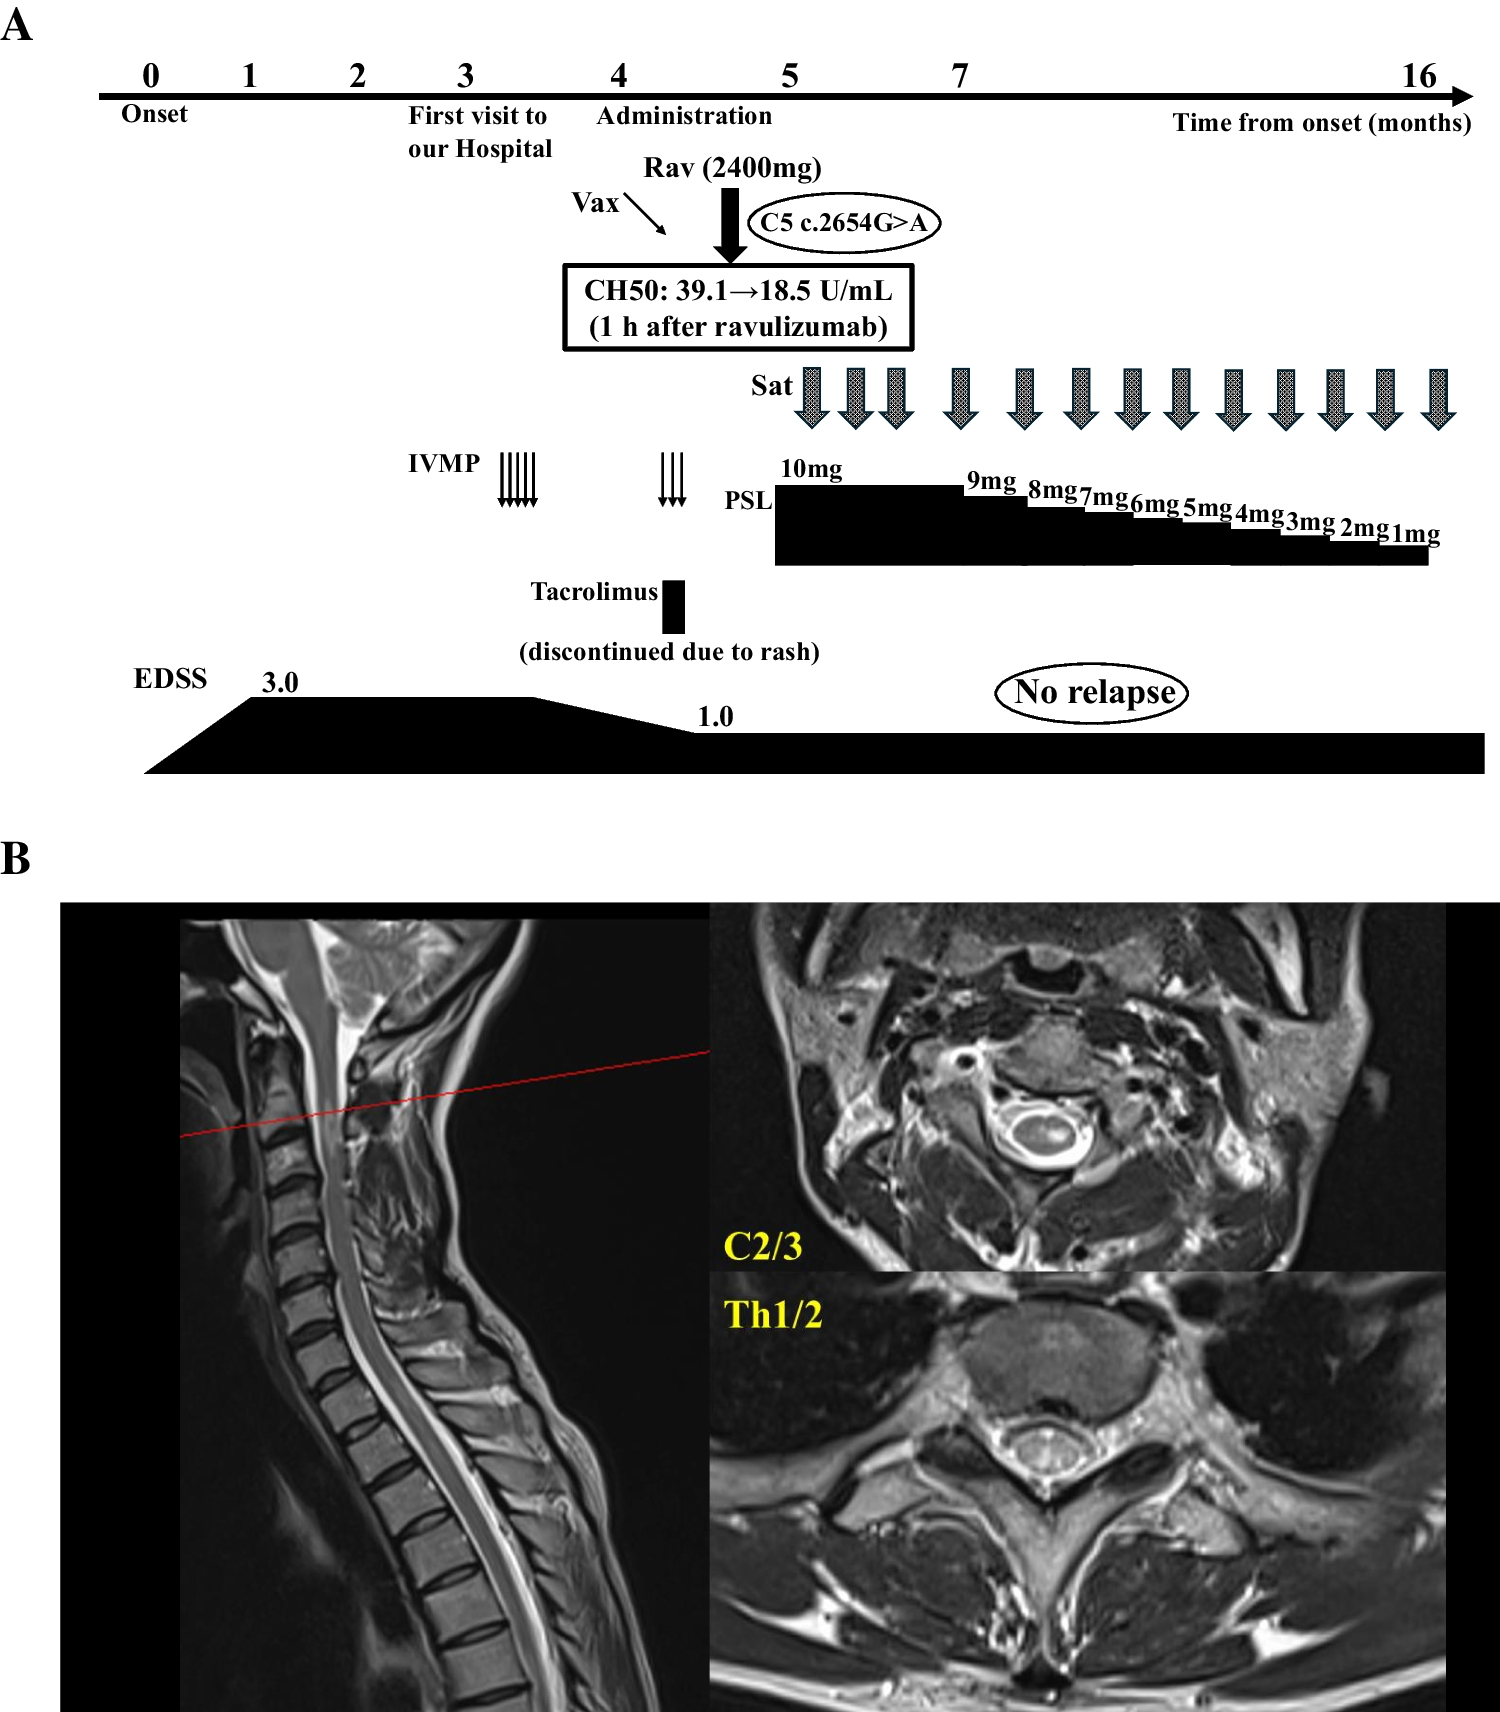

Purpose: Bilateral damage of fornix bodies has been reported in a few cases of brain tumors and in exceptional cases of ischemia. Methods: a 73-year-old man presented with acute right ataxic hemiparesis and right hypoesthesia. Brain MRI showed an acute ischemia of both fornix bodies and of the left posterior lateral thalamus, along with a septum pellucidum (SP) cyst. MR angiography revealed a 7-mm long stenosis of the initial P2 of the left posterior cerebral artery. Neuropsychological evaluation documented an amnestic syndrome. Fornix bodies and posterolateral thalamus are supplied by the medial and lateral branches of posterior choroidal artery, arising from the initial P2. As our patient presented a single intracranial vascular lesion on MR-angiography, i.e. long stenosis at the initial P2, left thalamic ischemia and ischemic lesions of both fornix bodies were due to the unpaired variation of that artery. Moreover, this fornix ischemia occurred in association with SP cyst, which did not favored the ischemia, but resulted in a unique and unreported pattern, because of the configuration and relationships of the fornix. The amnestic syndrome related to the fornix ischemia in our patient was non-specific. Conclusions: unreported condition of infarct of both the fornix bodies- responsible for acute anterograde amnesia- and of left inferolateral and posterior thalamic territories, related to an atheromatous stenosis of the initial left P2 posterior cerebral artery. The fornix bodies infarct occurred in a patient with a large SP cyst, which gives a particular pattern, non-previously described.